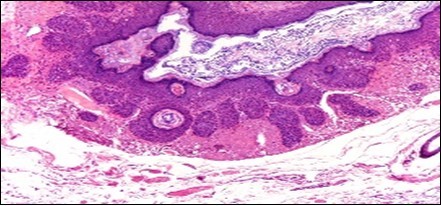

A cogent tissue specimen demonstrates typical features of comedones as follicular ostia distended and impacted with keratin. Significant histological manifestations are the occurrence of enlarged, grouped, distended follicular ostia demonstrating an absence of hair shafts along with impaction of laminated keratin. Base of the follicular invaginations may or may not delineate singular, rudimentary glandular structures. Miniature cysts, cystic invaginations and occasional enlarged cysts can be encountered. Cystic articulations are diverse and preponderantly layered by keratinizing, stratified squamous epithelium. Hyperkeratosis or epidermolytic hyperkeratosis and acanthosis of superimposed epidermis can concur although the lesion is devoid of parakeratosis or dyskeratosis5, 6.

Nevus comedonicus demonstrates immune reactivity to cytokeratin, simulating the expression of normal cutaneous surfaces. Generally encountered within the granular epidermal layer, immune reactivity for filaggrin is demonstrable within the entire epidermal thickness of closed comedones, a molecular which can be implicated in the genesis of nevus comedonicus6, 7. Electron microscopy demonstrates an enhanced quantification of Langerhans cells, numerous kerato-hyaline granules along with an abundance of tonofilaments within upper portion of stratum spinosum. Incompletely differentiated arrector pili muscles are impacted with intracellular glycogen particles6, 7. Figure 1, Figure 2, Figure 3, Figure 4, Figure 5, Figure 6, Figure 7, Figure 8, Figure 9, Figure 10.

Figure 1.Nevus comedonicus with grouped, dilated follicular ostia, impacted with keratin and a layering of hyperkeratotic stratified squamous epithelium11.

Figure 2.Nevus comedonicus with plugging of follicular ostia, keratinous impaction and a lining of hyperkeratotic stratified squamous epithelium11.